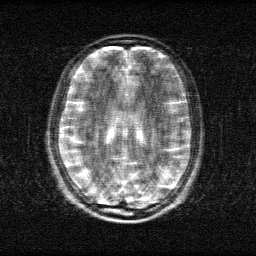

Method: CPU_baseline | Mismatch: nominal (nominal=True, perturbed=False)

Ground Truth

Measurement

Reconstruction